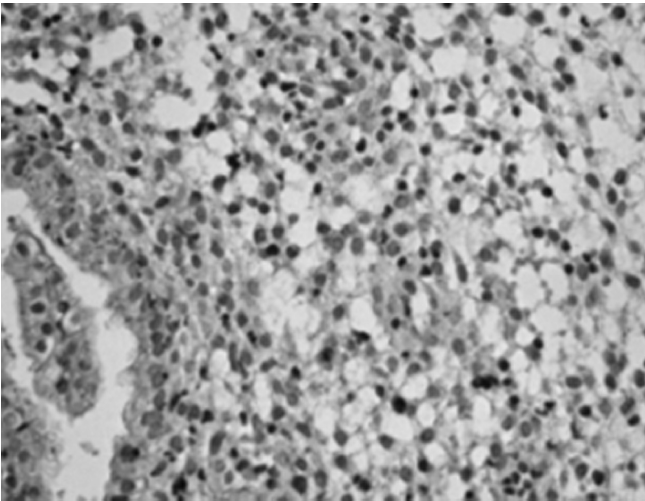

We analyzed the IHC results of a 29-year-old patient, who was admitted with primary infertility. The patient had morphologically confirmed fibroglandular polyps of the endometrium, which was previously identified by ultrasound examination.

Based on the findings of IHC analysis, ER and PR expression in the endometrium correspond to menstrual cycle phases (Figure 3). In addition, signs of chronic inflammation (i. e., chronic endometritis) with a weak autoimmune component (Figures 4-10) are revealed.

Fig. 3. Endometrial scraping during the late secretory phase at 100× magnification